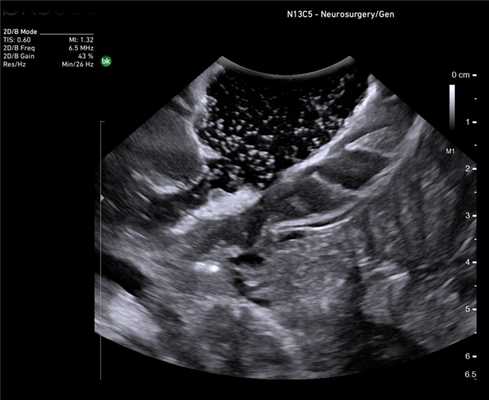

Клинический пример N2. Пациентка Р. находилась на лечении в ГУРОНЦ РАМН. При прохождении обследования был установлен диагноз рак толстой кишки. По данным ультразвуковой компьютерной томографии на фоне выраженной диффузной неоднородности паренхимы печени очаговые образования не определялись. При проведении ангиографии и компьютерной томографии так же убедительных данных за наличие метастазов в печень получено не было. При интраоперационном ультразвуковом исследовании были выявлены два очага, характерными особенностями которых являлись малые размеры (0,2 - 0,4 см), а так же нечеткость контуров и изоэхогенность структуры (рис. 1 а,б).

Рис. 1. Метастатические очаги (стрелки) в печени при интраоперационной ультразвуковой томографии.